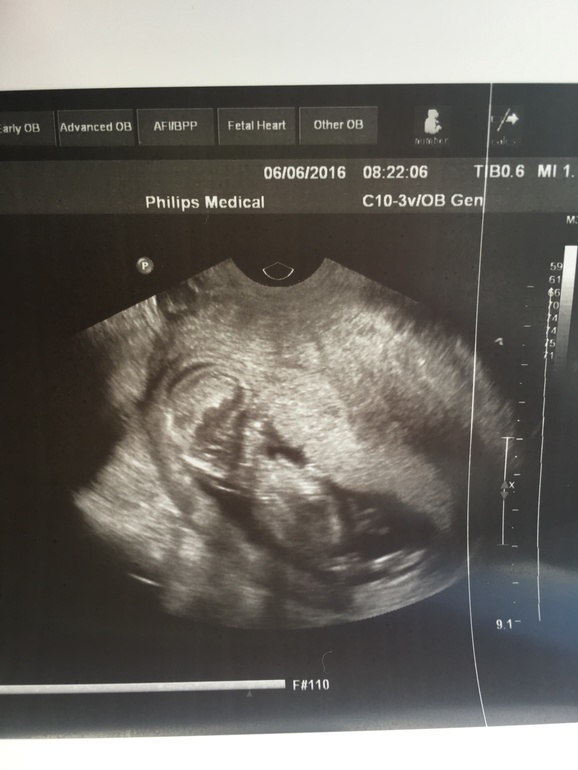

Первый скрининг 12,6

Долгожданная встреча состоялась. Ходили с папой, Папа остался доволен....сидел улыбался) С малышом все хорошо. Был довольно спокойный, сосал пальчик)

КТР - 65

ЧСС - 156

Носовая кость - визуализируется (но не написали сколько мм)

Толщина воротникового пространства 1,9

Локализация по передней стенке ( с Глебом тоже было так)

Рубец от КС хороший 10 мм